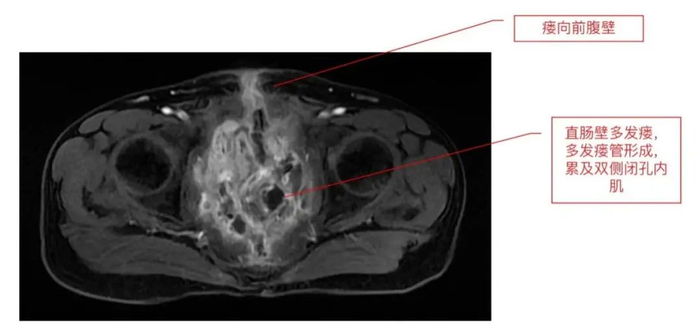

董先生的病情复杂、病程长,有多次盆腔手术史及放射治疗史。全盆器官切除手术后因“空盆腔脏器综合征”及“盆腔放射性损伤”等出现了直肠吻合口-盆腔小肠-尿道残端-腹壁-阴茎复杂瘘,导致盆腔解剖结构不清。先后经历腹盆腔六次手术,再次进腹手术难度可想而知。对绝大多数胃肠外科医生来说,此病例无疑是“烫手山芋”。

近期,马腾辉团队为董先生进行了剖腹探查手术,术中探查发现盆腔肠管多发粘连,伴回肠-结肠-皮肤-阴茎-盆腔-代直肠吻合口瘘并多发瘘管。手术完整切除了盆腔放射性损伤严重的病变小肠、病变代直肠吻合口,并清除盆腔脓肿。为消除空盆腔间隙,清除盆腔病损后,将直肠远端封闭,将自体大网膜内移植填塞于盆腔间隙,最后进行全盆底重建修复,在为患者解除病痛的同时,也降低了再次复发的可能。手术历时5个小时,出血仅约300ml。

此次董先生手术的难点在于:盆腔放射性损伤的复杂肠粘连松解;确定性肠瘘切除及盆腔复杂窦道清除;代膀胱的保护和输尿管位置改变后的保护;盆腔大出血的防控等。